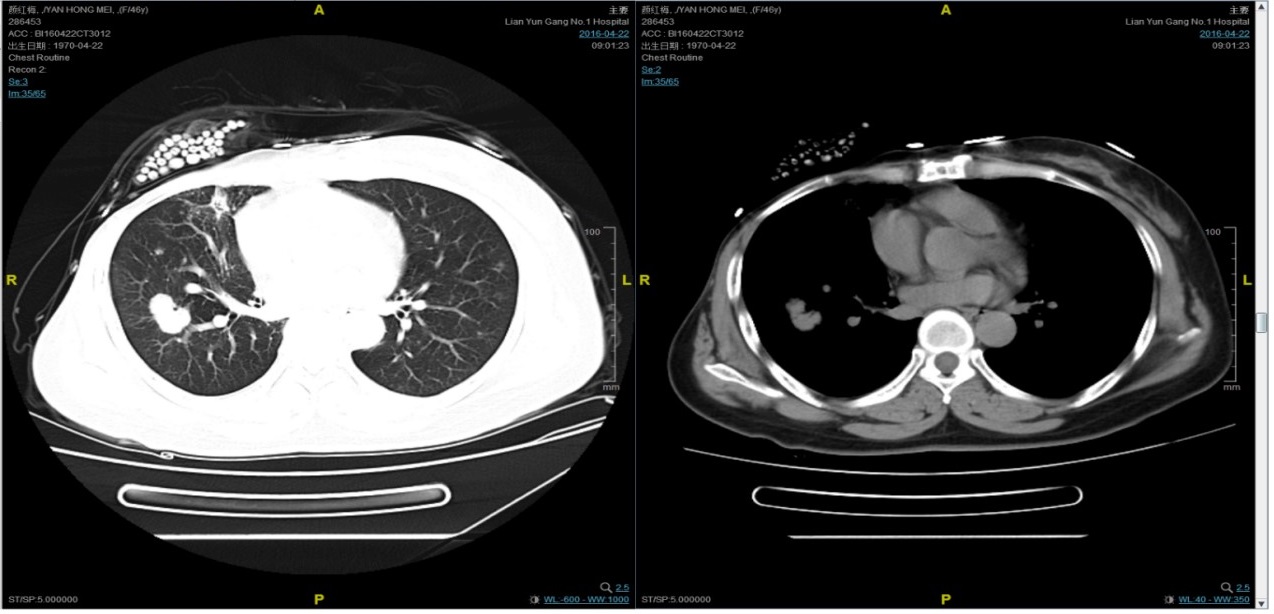

从2016-2-19开始给予紫杉醇+曲妥珠单抗治疗,紫杉醇240mg,3周重复,曲妥珠单抗330mg三周重复。患者末次应用曲妥珠单抗和紫杉醇时间为2016-6-24,紫杉醇共应用4周期。

期间2016-4-22复查CT如下:

2016-7-5化疗结束后复查CT,疗效评价稳定。